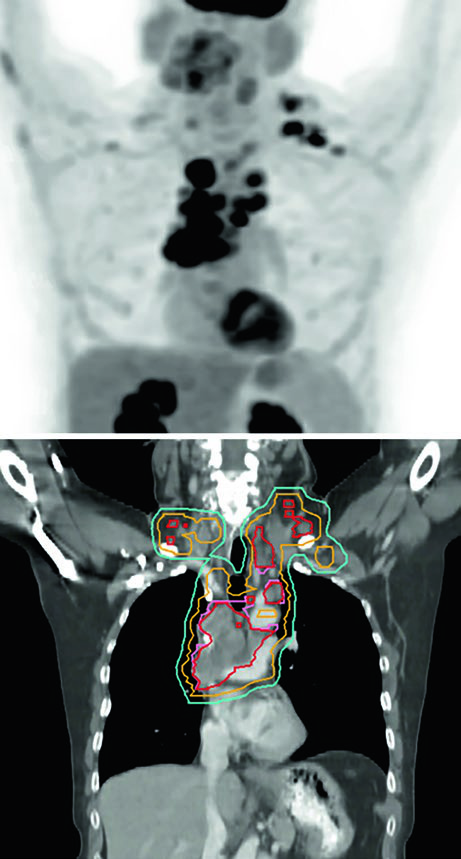

A Figura 13.5 do capítulo mostra um tumor de 5,8 cm no LSE com positividade nos níveis 5 e 10L. O campo limitado conforme Lung ART é o utilizado, com 54 Gy/30fx.

Replanejamento adaptativo: quando a anatomia muda durante o tratamento

Tumores obstrutivos que causam atelectasia podem resolver parcialmente durante o tratamento à medida que a radioterapia reduz o volume tumoral e o pulmão reaeração. Esse fenômeno, documentado nas CBCT de verificação, pode expor tecido pulmonar previamente colapsado à dose prevista para o tumor, alterando dramaticamente a distribuição de dose.

O replanejamento adaptativo deve ser considerado quando a CBCT mostra mudança anatômica significativa — expansão pulmonar ipsilateral, redução de derrame ou colapso em resolução. O caso da Figura 13.7 ilustra uma lesão metastática tratada com 45 Gy/15fx: a reaer ação pulmonar durante o tratamento exigiu replanejamento para proteger o pulmão recém-arejado.

Não existe protocolo universal para o gatilho do replanejamento adaptativo. Na prática, CBCT semanal com revisão pelo planificador e pelo oncologista é o mínimo razoável. Qualquer mudança visual significativa no contorno pulmonar ou mediastinal justifica recalcular os DVHs antes de continuar.